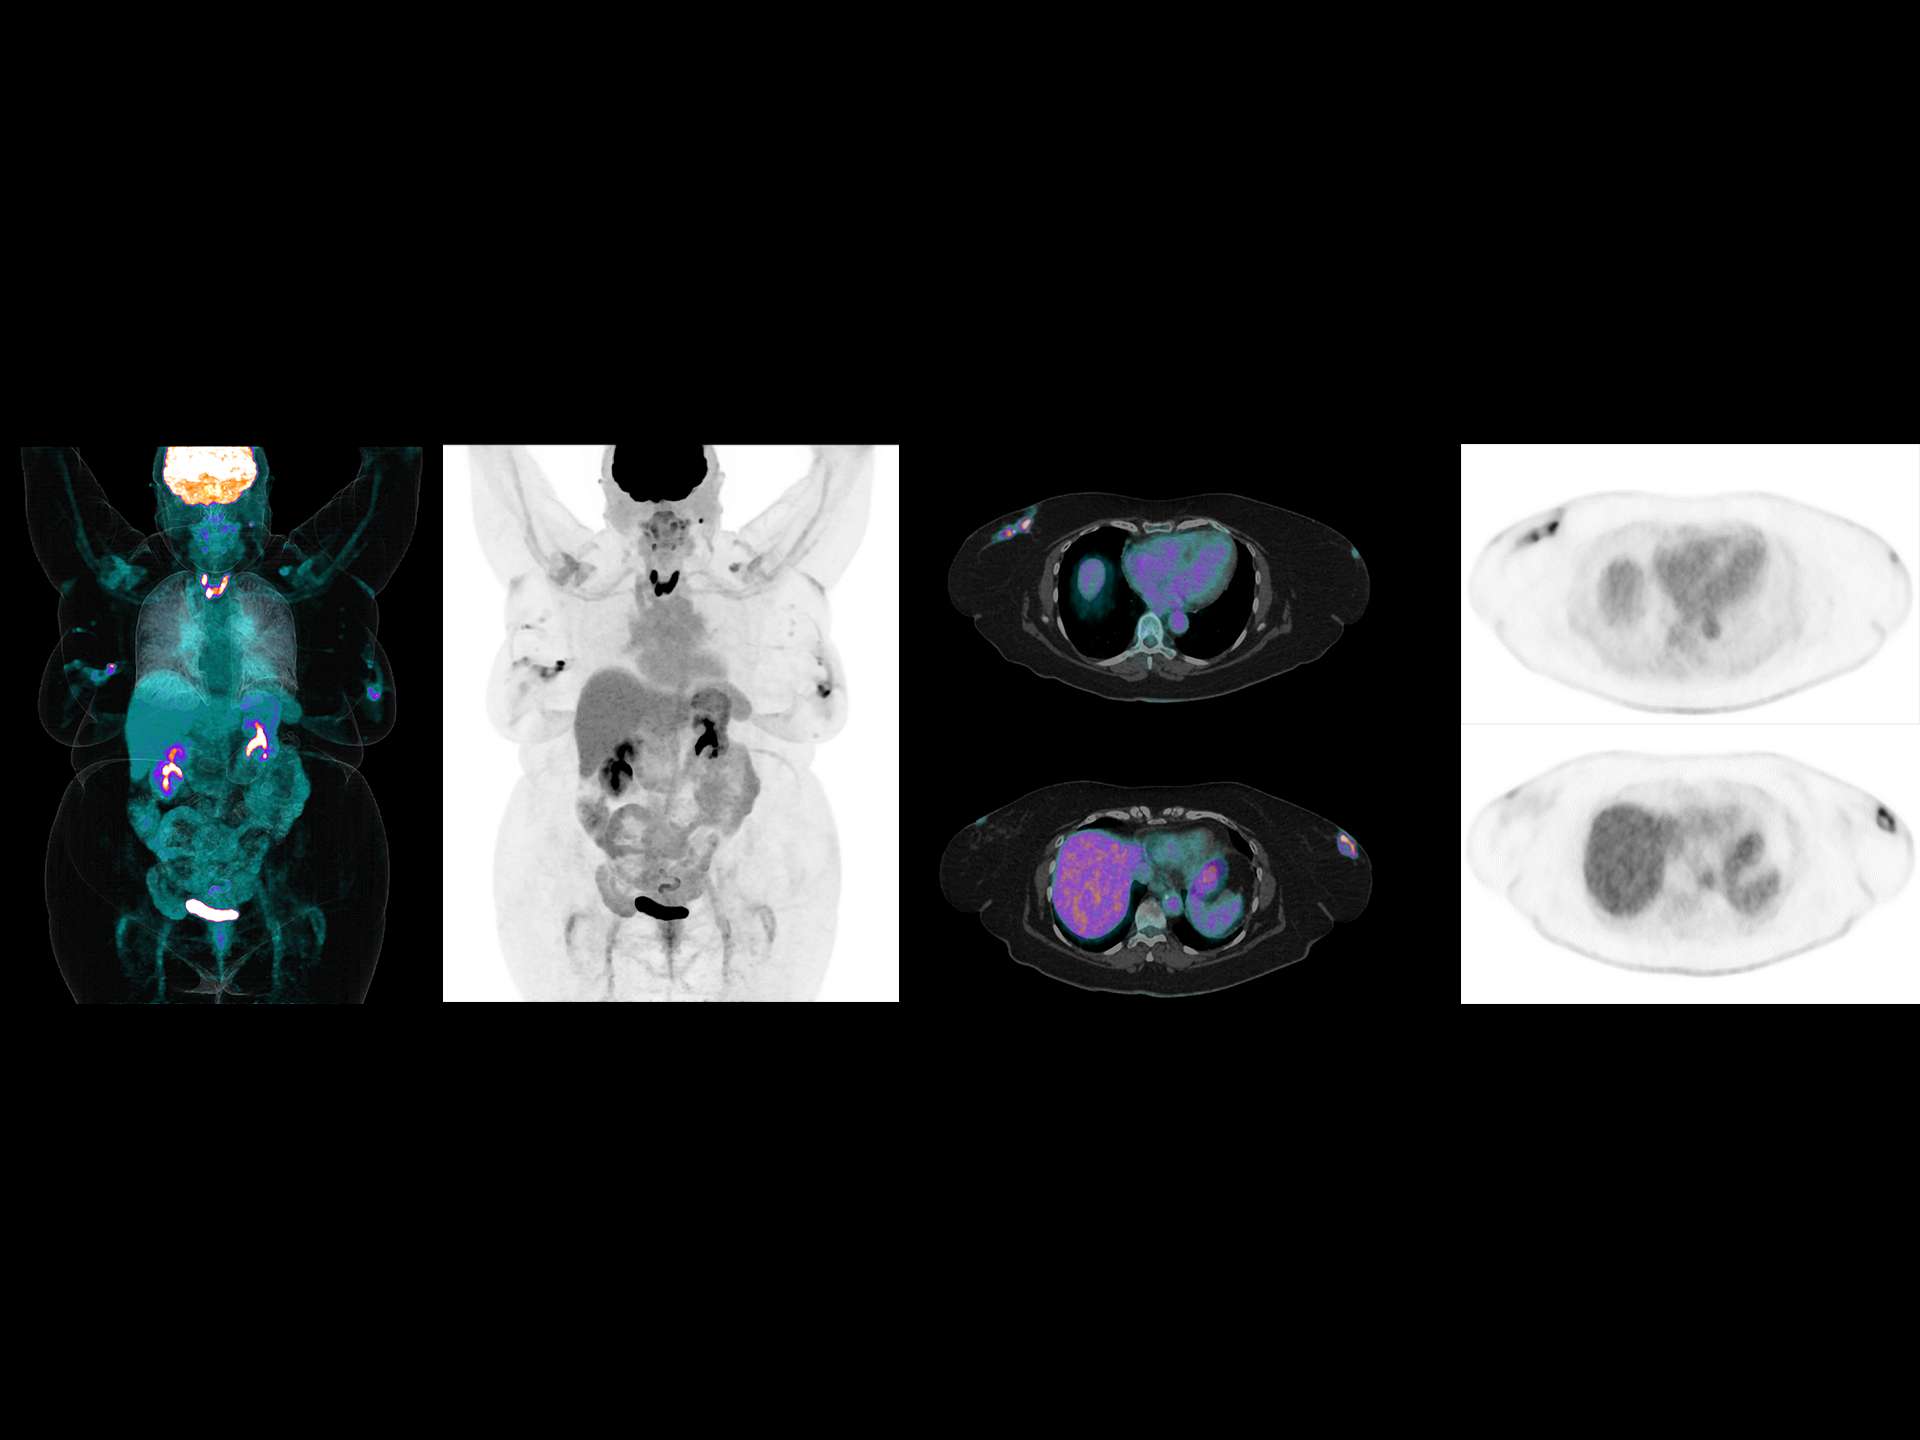

Exceptional NEMA spatial resolution delivered by the finest crystal size of 2.76 mm in the industry.

Leading TOF resolution that boosts small lesion detectability and clarity.